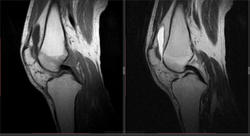

Мужчина 1963 г.р. Жалуется на боль в левом коленном суставе около 6 мес, в последний месяц стало совсем тяжко. Со слов заболел зимой, когда во время прогулки коленки сильно замерзли. Сам думаю на асептический некроз, но смущает множественность поражения.

Дмитрий, я в заболеваниях суставов не дока, но трабекулярный отек вкупе с выпотом может быть обусловлен воспалительными изменениями , но полностью начальные проявления аваскулярного некроза не могу отрицать.

я бы не поставил аваскулярный некроз. если исключена травма, дифференцировать с артритом.

Хрящ не поврежден, для артрита...